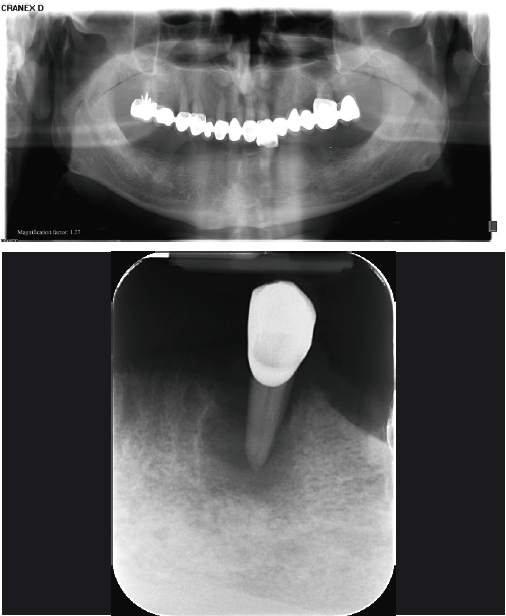

Grundsätzlich wird davon ausgegangen, dass bei einem Restknochen von weniger als 5,0 mm Breite im Zusammenhang mit Implantatbehandlungen Knochenaufbaumaßnahmen erfolgen müssen, um ein ausreichend dimensioniertes Knochenlager für die Implantate zu erhalten [28]. Im vorliegenden Fall erfüllte der Alveolarfortsatz im Bereich der Insertionsstellen der Implantate knapp die Voraussetzungen einer Implantation ohne zusätzliche Augmentationsmaßnahmen. Wir entschlossen uns in Absprache mit dem Patienten für die Extraktion des Zahnes 33 und für eine anschließende implantatgestützte prothetische Versorgung des Unterkiefers auf vier Implantaten im Eckzahn- und Molarenbereich beidseits ohne zusätzliche Augmentationsmaßnahmen.

Die Implantatinsertion wurde unter Lokalanästhesie und unter direkter Sicht mit Bildung eines Mukoperiostlappens durchgeführt. Das offene Vorgehen wurde gewählt, da eine fortgeschrittene Resorption des knöchernen Alveolarfortsatzes in oro-vestibulärer Richtung vorlag und auf diese Weise eine sehr gute Beurteilung der Knochenkonturen und der Qualität des Knochens sowie eine Implantatpositionierung unter direkter Sicht ermöglicht wurden [33-35]. Es wurden BEGO Semados® RSX Implantate (BEGO Implant Systems) mit den Standarddurchmessern 3,75 mm (regio 036 und 043) und 4,10 mm (regio 046 und 033) verwendet. Die Implantation erfolgte freihändig nach dem Standardprotokoll des Herstellers. Alle Implantate wurden, mit Ausnahme des Implantats in regio 043, epikrestal am bukkalen Aspekt eingesetzt (Abb. 4). Da der Alveolarkamm sattelförmig gestaltet war, lag der Implantathals bei allen Implantaten approximal jeweils etwa 1,0 mm subkrestal. Das Implantat in regio 043 wurde nach lingual hin ca. 2,0 mm subkrestal inseriert.

Aufgrund des guten vertikalen Knochenangebotes konnten im Eckzahnbereich 11,5 mm lange Implantate und im Seitenzahnbereich Implantate mit der Länge von 10 mm verwendet werden. Dabei war eine Abwinkelung der Implantate im Seitenzahnbereich – wie sonst bei der klassischen All-on-4® Methode üblich – nicht notwendig (Abb. 5).